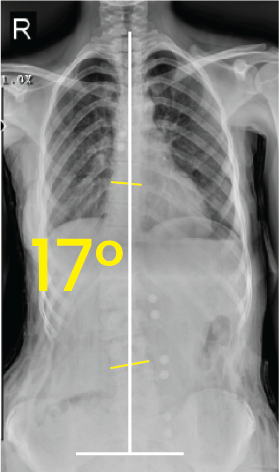

Bel omurgasında 33 derecelik eğrilik gösteren skolyozlu insan göğüs ve karın röntgeni.Göğüs bölgesinde 17 derece eğiklik gösteren omurga röntgeni görüntüsü.

Toraks röntgen görüntüsünde 30 derecelik skolyoz eğriliği sarı açılarla ve beyaz çizgilerle işaretlenmiş.Göğüs ve bel bölgesini gösteren röntgen, omurga eğriliğinin 14 derece olduğunu belirtir.